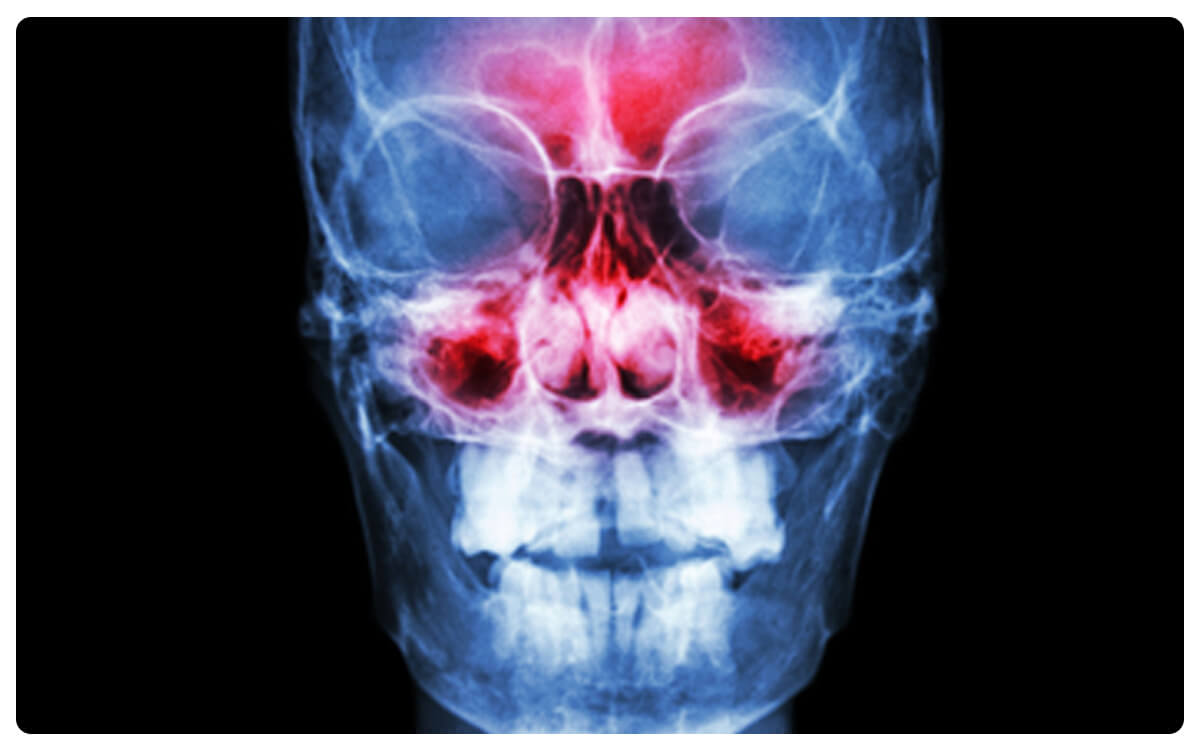

La Radiografía de Senos Paranasales en Tres proyecciones se posiciona como una herramienta esencial en la radiología diagnóstica, brindando una visión completa y detallada de las estructuras sinusales y posibles afecciones. A través de la emisión controlada de radiación, esta técnica no invasiva proporciona imágenes bidimensionales en diferentes ángulos, permitiendo la evaluación exhaustiva de los senos paranasales desde perspectivas frontales, laterales y oblicuas.

La Radiografía de Senos Paranasales en tres proyecciones desempeña un papel crucial en el diagnóstico y seguimiento de sinusitis, pólipos, obstrucciones y otras patologías que afectan esta área, proporcionando información valiosa para la toma de decisiones clínicas informadas y el manejo adecuado de las afecciones relacionadas con los senos paranasales.